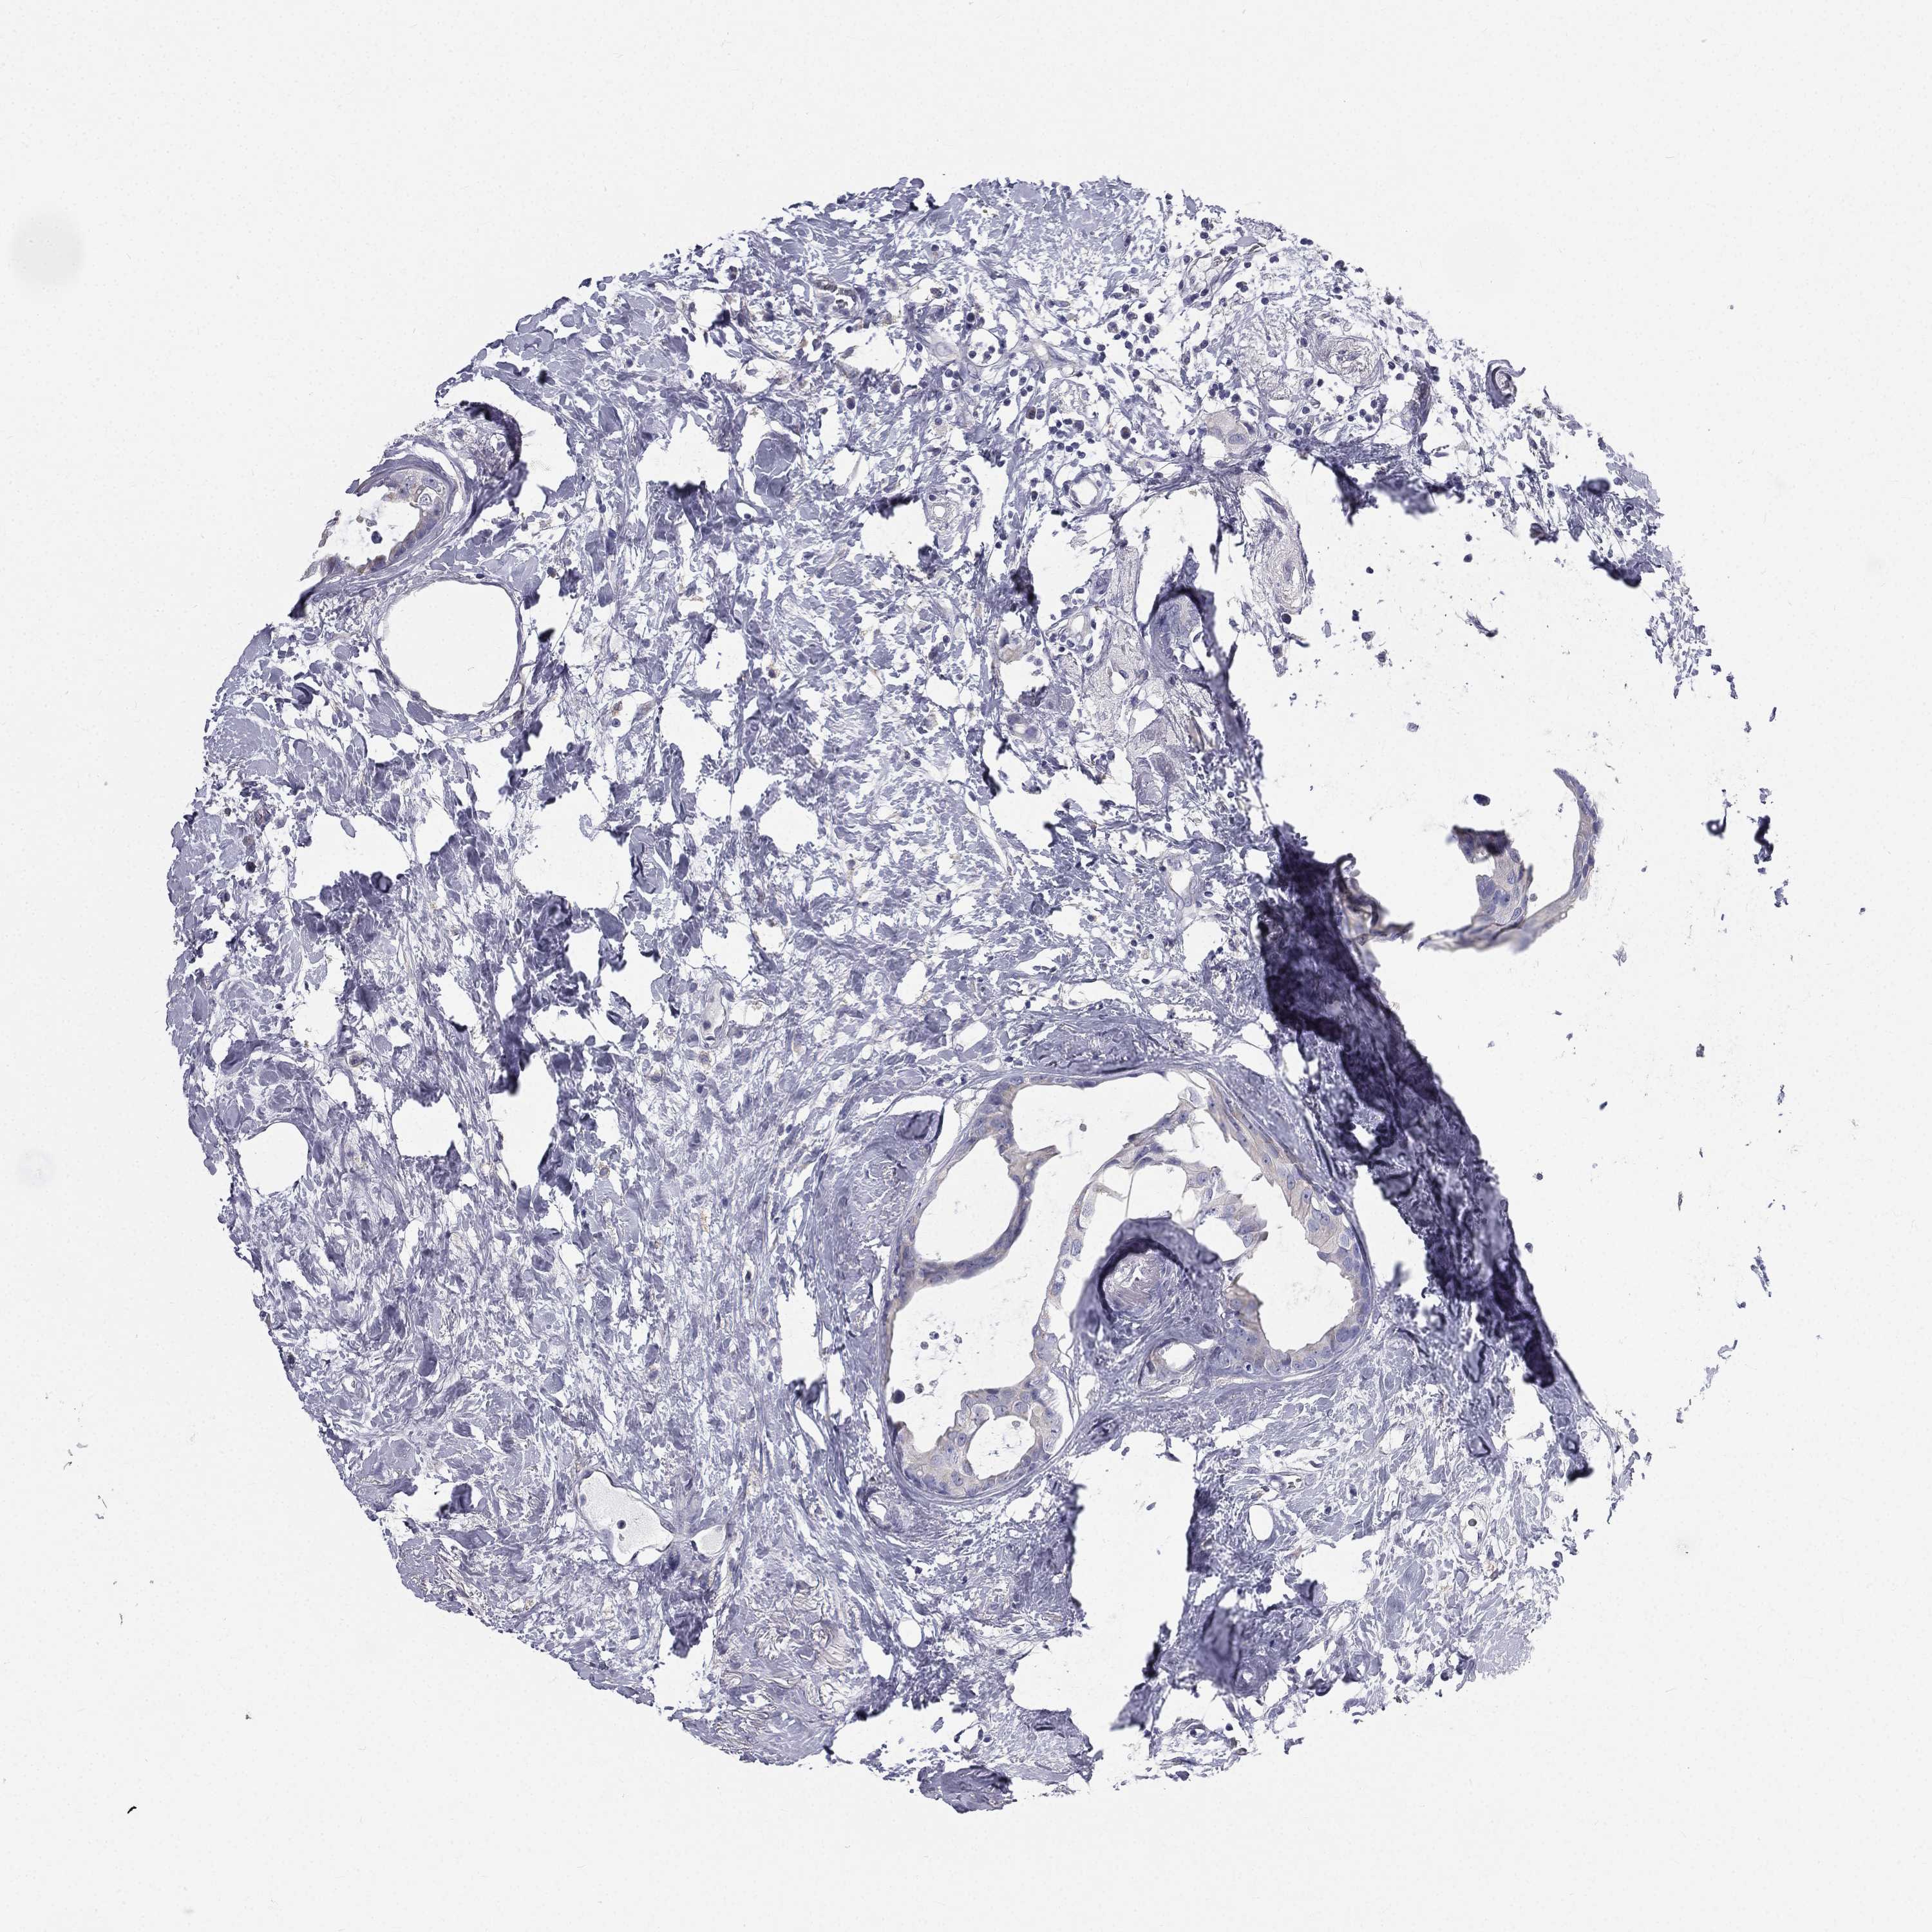

BRCA TCGA BRCA VALIDATION PROTEIN EXPRESSION

ANTIBODIES

AND

VALIDATION